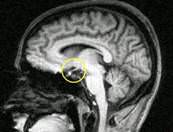

Необходимо УЗИ всех доступных для исследования органов и систем — как для оценки их текущего состояния, так и для дифференциальной диагностики. Рентгенография и МРТ черепа позволят визуализировать травмы, изменения турецкого седла, опухоли, оценить состояние сосудистой системы головного мозга.